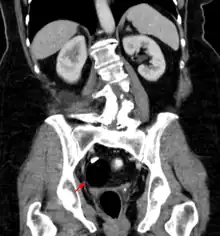

CT showing a teratoma of the ovary: fatty formation with a smooth boundary, with a dense part, possibly a tooth.

Teratomas are thought to originate in utero, so can be considered congenital tumors. Many teratomas are not diagnosed until much later in childhood or in adulthood. Large tumors are more likely to be diagnosed early on. Sacrococcygeal and cervical teratomas are often detected by prenatal ultrasound. Additional diagnostic methods may include prenatal magnetic resonance imaging. In rare circumstances, the tumor is so large that the fetus may be damaged or die. In the case of large sacrococcygeal teratomas, a significant portion of the fetus' blood flow is redirected toward the teratoma (a phenomenon called steal syndrome), causing heart failure, or hydrops, of the fetus. In certain cases, fetal surgery may be indicated.

Beyond the newborn period, symptoms of a teratoma depend on its location and organ of origin. Ovarian teratomas often present with abdominal or pelvic pain, caused by torsion of the ovary or irritation of its ligaments. A recently discovered condition where ovarian teratomas cause encephalitis associated with antibodies against the N-methyl-D-aspartate receptor antibody (NMDAR) - often referred to as "anti-NMDA receptor encephalitis", was identified as a serious complication. Patients develop a multistage illness that progresses from psychosis, memory deficits, seizures, and language disintegration into a state of unresponsiveness with catatonic features often associated with abnormal movements, and autonomic and breathing instability.[34] Testicular teratomas present as a palpable mass in the testis; mediastinal teratomas often cause compression of the lungs or the airways and may present with chest pain and/or respiratory symptoms.